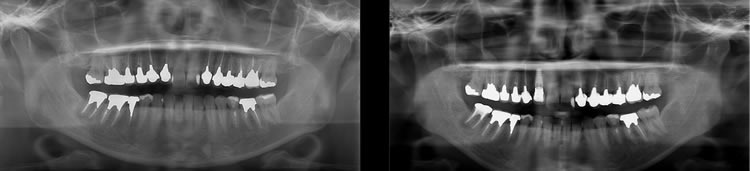

ファイナルレストレーション